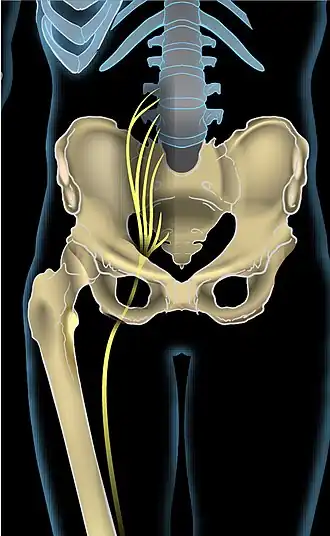

| Vista anterior do nervo ciático a descer a perna direita | |